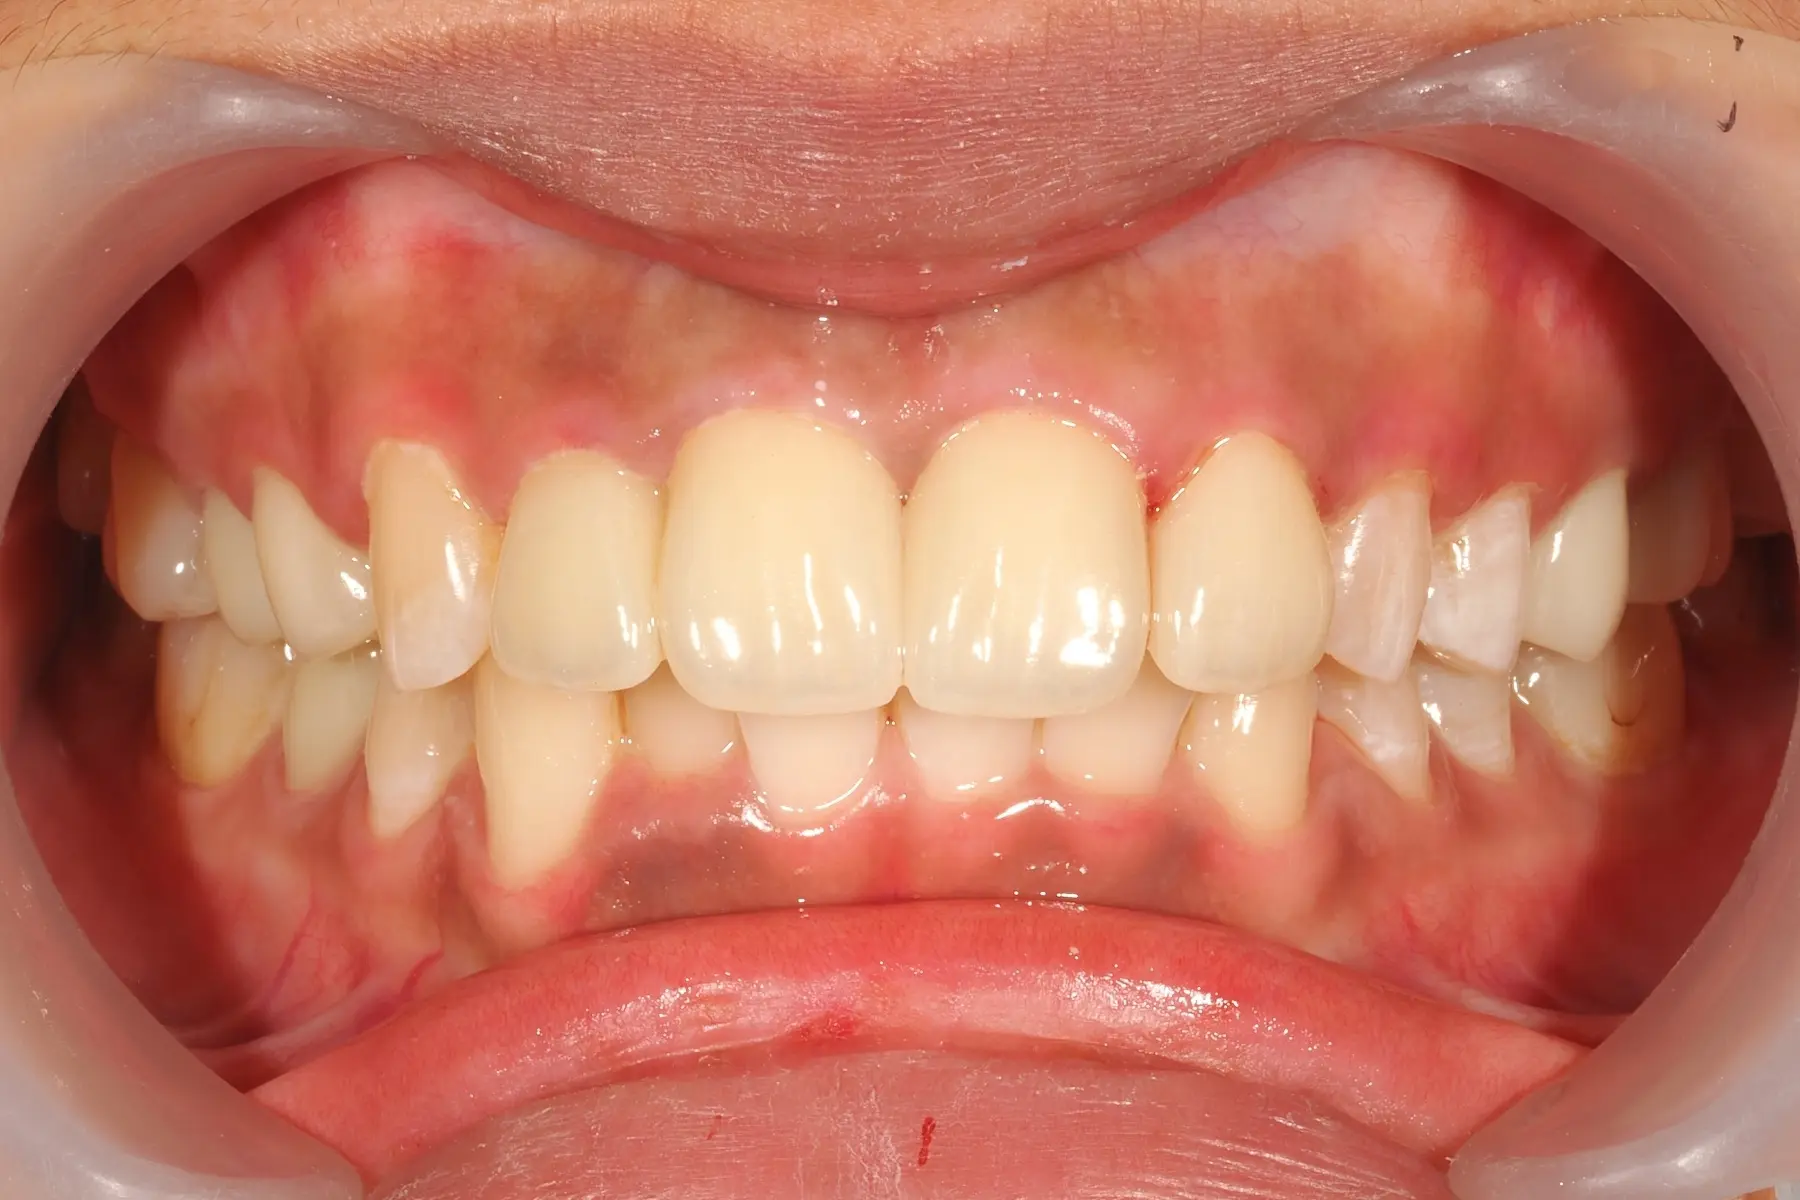

仿生全瓷冠

主治醫師

• 陳暐文

治療時間

約 1.5 個月

主訴

門牙曾接受根管治療,尚未裝戴假牙,想評估全瓷冠修復